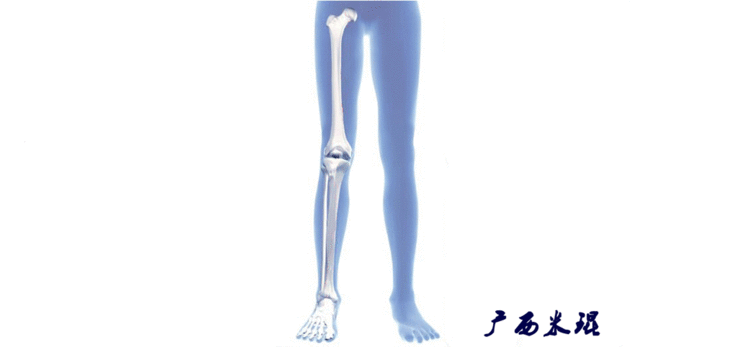

2、画出下肢的轴线确定髋关节、膝关节、踝关节的中心点后,我们才能了解下肢的几个轴线。(1)解剖轴股骨和胫骨的骨干中线为解剖轴,股骨解剖轴和胫骨解剖轴的夹角正常值为174°±1°。

(2)机械轴机械轴是连接近端和远端关节中心点的直线。

机械轴要分前后位及侧位,站立前后位(也就是冠状面)股骨头中心与踝关节中心的连线通过膝关节中心,这是下肢的机械轴线,也就是下肢力线,常说Mikulicz线。冠状面的力线评估在临床工作中最常用、最基础、最重要。

站立侧位(矢状面)股骨头中心与踝关节中心的连线也通过膝关节中心,这也是下肢的机械轴线,这也是下肢力线。

(3)垂直轴也就是下肢的负重轴,它是身体的纵轴线,与地面垂直,由于双髋比双踝的距离宽,所以垂直轴与下肢力线(机械轴)存在3°的外翻。

开始接触时可能我们对这些轴有点混乱,通过下面的这张图片就能清楚的了解下肢几个轴之间的关系。